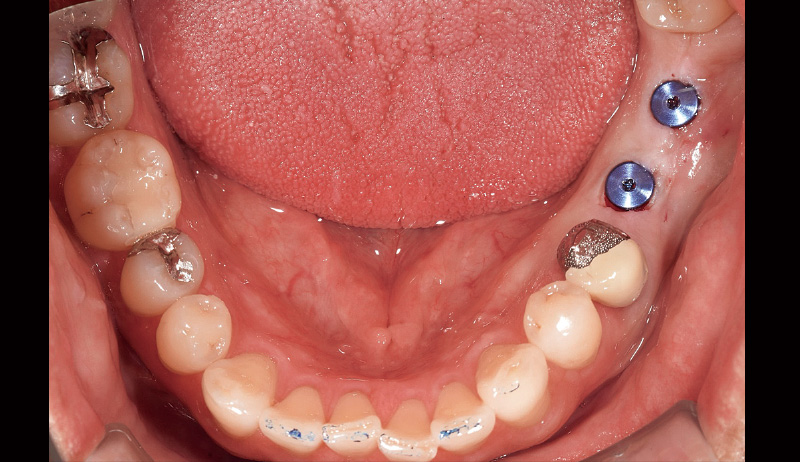

主訴:左下の奥歯で噛めるようになりたい(図6, 7)。

₆、₇にインプラントを埋入し左側の咬合を得る治療計画を立案。φ4.5長さ9.5mmのSPIイニセルインプラント エレメントRCを埋入した(図8)。まずはここで初期固定を得られたのでヒーリングキャップにて封鎖した(図9)。今回は勤務医たちへの指導の意味もあり、ガイデッドサージェリーにて行った。そして4週目でクローズドトレーにてシリコン印象を行い補綴装置をセットした(図10,11)。CBCT撮影を行い骨レベルの状態を確認し、機能的審美的にも問題ないことがわかっている(図12, 13)。

![[写真] オペ後の口腔内写真](/academic/dentalmagazine/wp-content/uploads/sites/2/2025/09/194-8_photo09.jpg)

図9 オペ後の口腔内写真 -